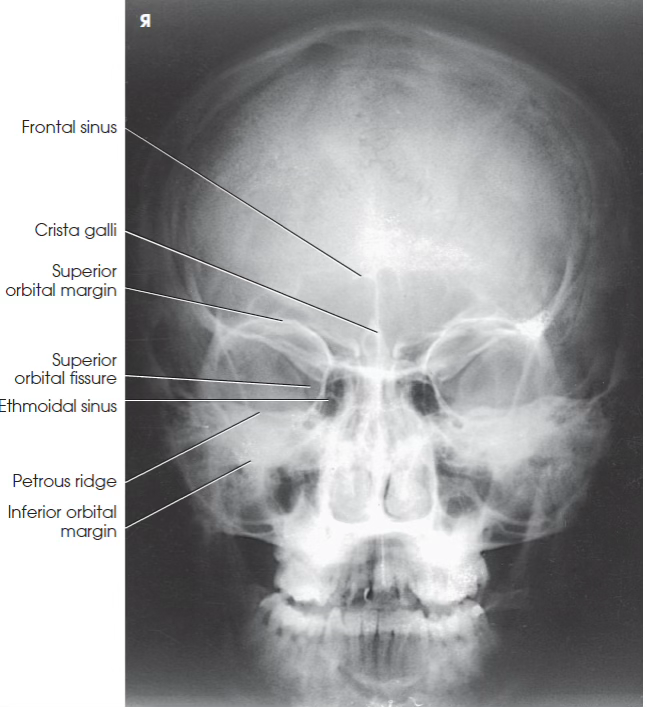

What view is this?

PA skull